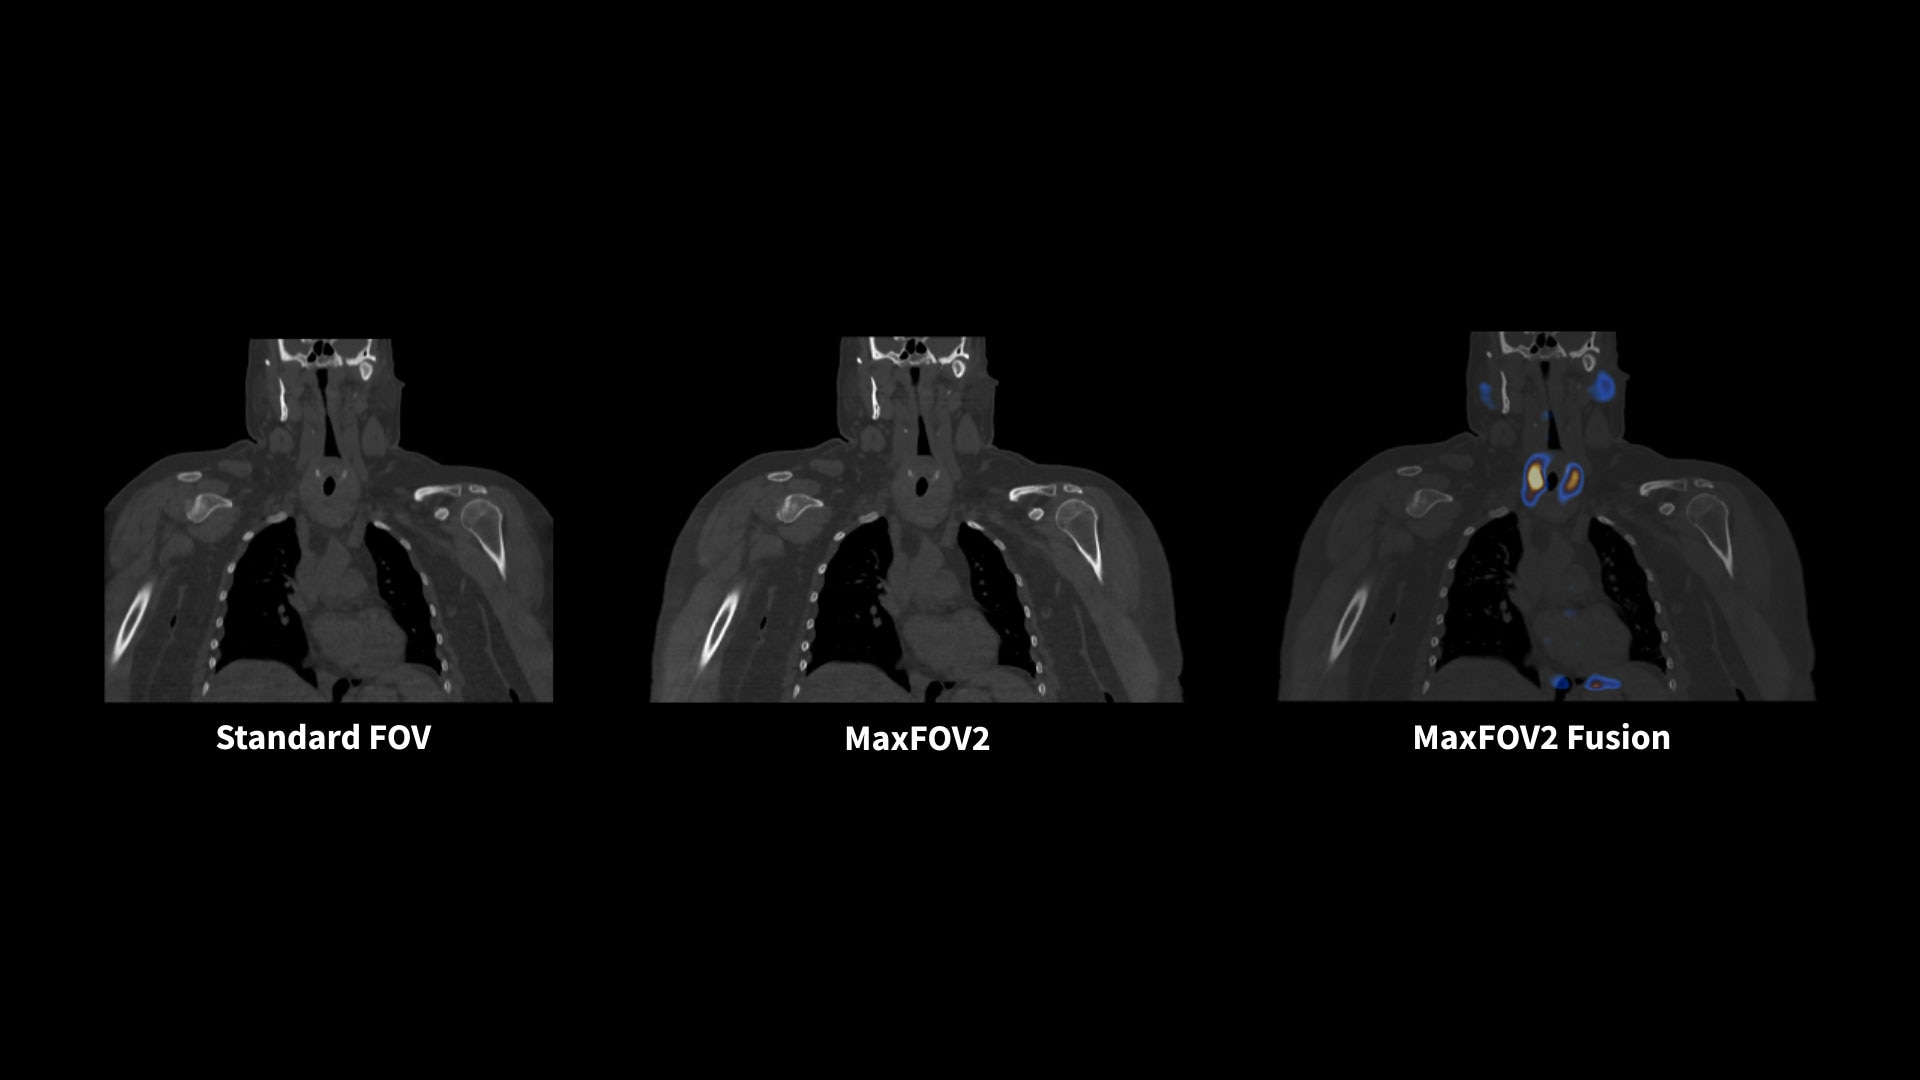

MaxFOV2* extends the display field of view (DFOV) from 50 cm to 75 cm¹⁴

When body size or positioning causes portions of the patient to extend outside the scan field of view, MaxFOV2's AI algorithm overcomes this, enabling the visualization of the patient's whole anatomy.

Aurora's 75 cm-wide CT bore opens up more space to high BMI patients for a comfortable scanning experience. The 75 cm CT display field of view with MaxFOV2* enables the visualization of high BMI patient's whole anatomy.¹⁴

*DL Automatic Kidney Segmentation and MaxFOV2 for Aurora options are not approved or cleared by the U.S. FDA. Not available for sale in the United States.

14. The image quality for the area outside the standard 50 cm scan field does not meet the image quality specifications shown in the technical data sheet and image artifacts may appear, depending on the anatomy scanned.